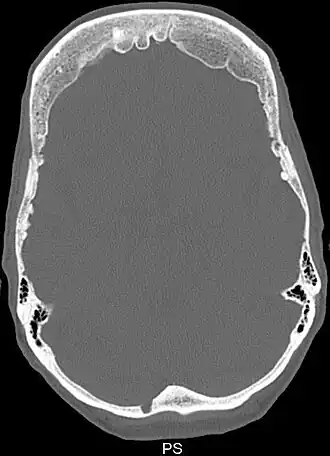

![]() Снимок компьютерной томографии черепа пациента с гиперостозом лобной кости | |

Синдром Морганьи — Стюарта — Мореля (метаболическая краниопатия) — состояние, связанное с широким спектром эндокринных проблем, включая сахарный и несахарный диабеты и гиперпаратиреоз[1]. Другие признаки и симптомы включают головную боль, головокружение, избыточное оволосение по мужскому типу, проблемы с менструацией, галакторею, ожирение, депрессию и эпилептические припадки[1][2]. Утолщение внутренней поверхности лобной части черепа является, как правило, начальной стадией заболевания, известного как hyperostosis frontalis interna[1][3].

Диагноз ставят на основе жалоб и клинической картины; также используют гистологические методы исследования. На рентгенограмме визуализируется утолщение лобной кости. Синдром Морганьи — Стюарта — Мореля дифференцируют в первую очередь от болезни Иценко — Кушинга и адипозогенитальной дистрофии.